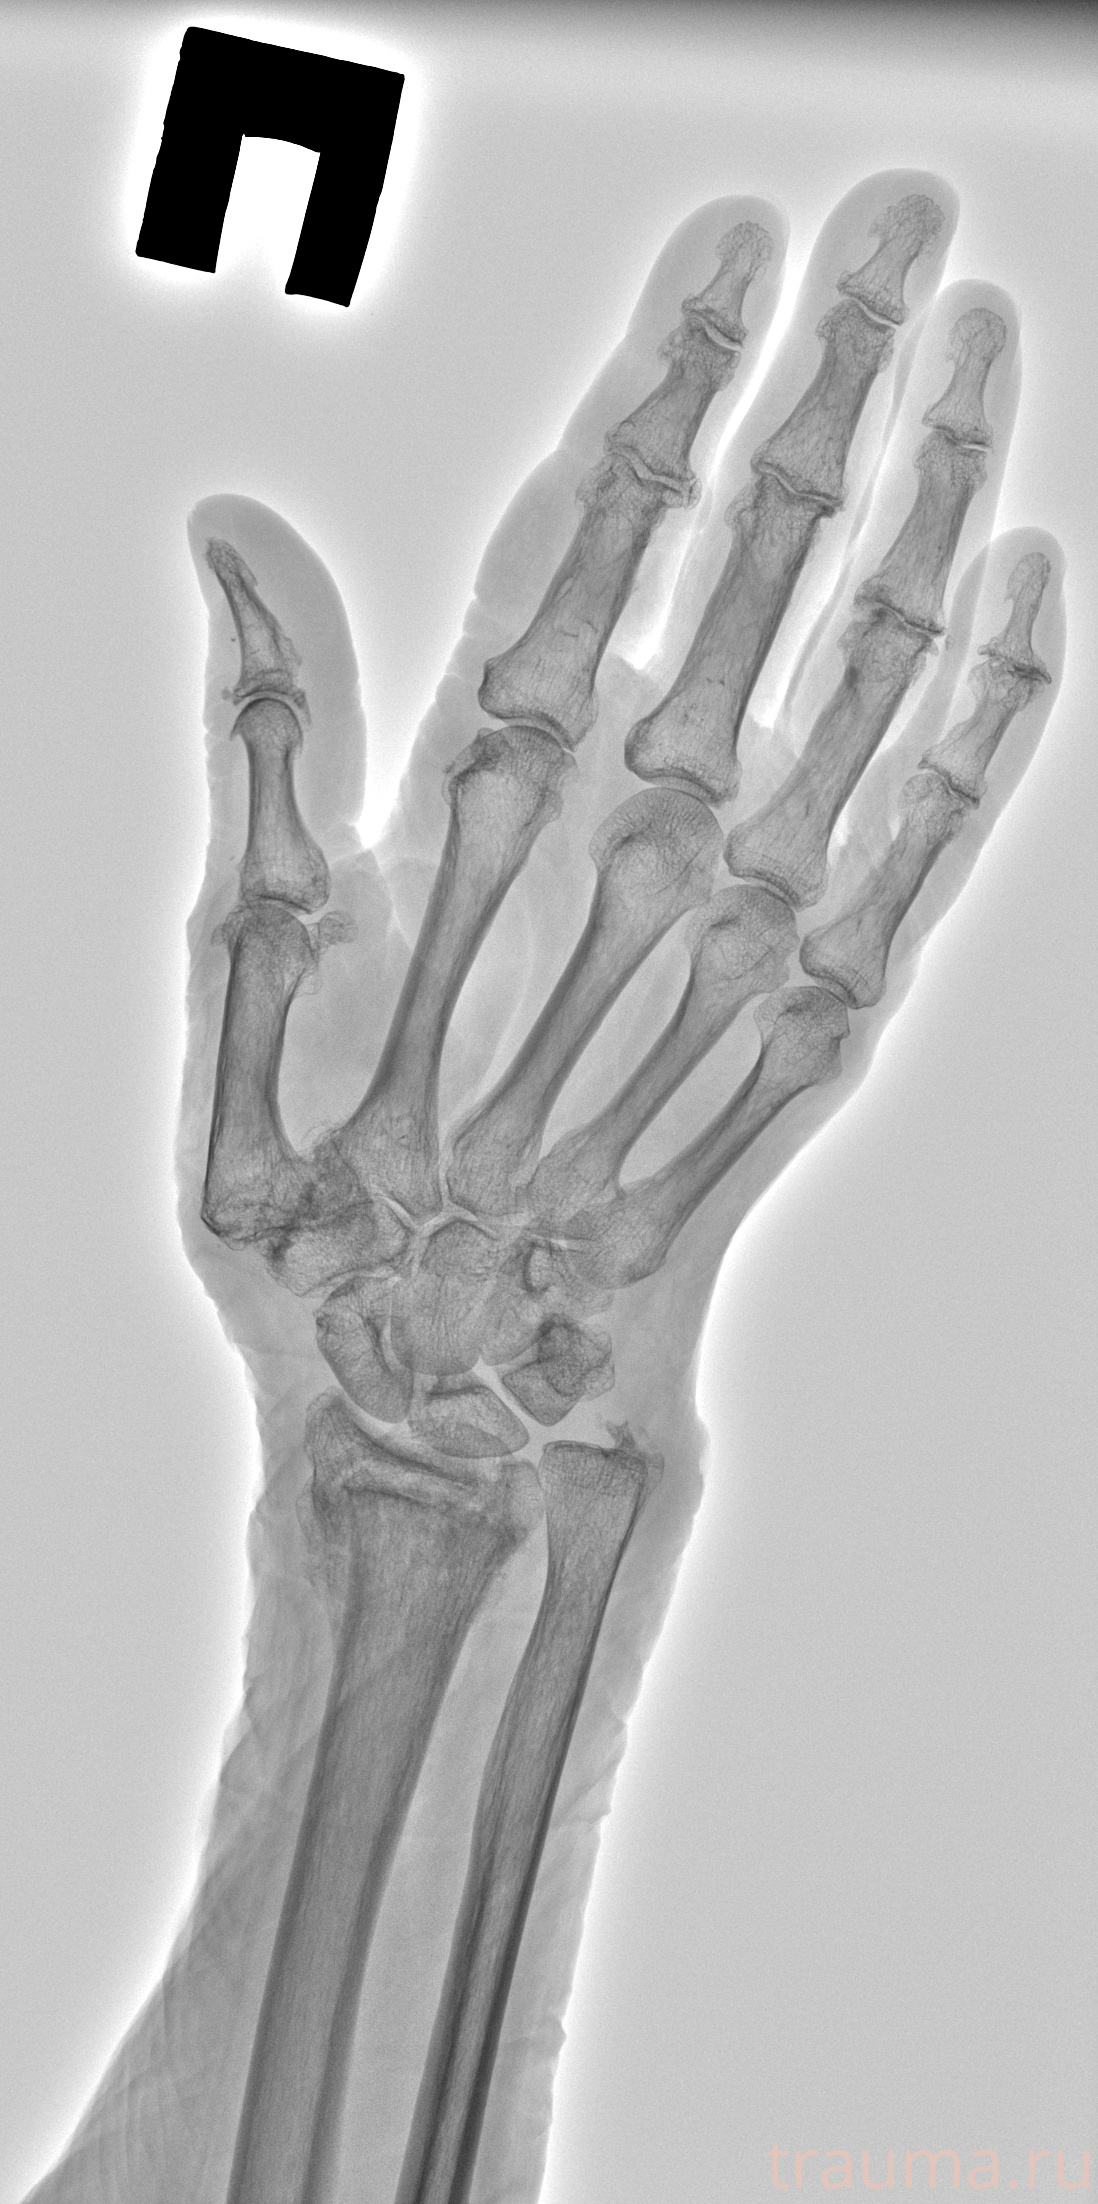

Рентген на дому: по вашему адресу приезжает врач-рентгенолог, травматолог-ортопед с мобильным рентгеновским аппаратом, проводит диагностику травмы или заболевания, делает необходимые рентгенограммы, дает рекомендации по дальнейшему лечению. Получить качественные снимки в домашних условиях возможно благодаря уникальной методике, разработанной МосРентген Центром для института  Склифосовского